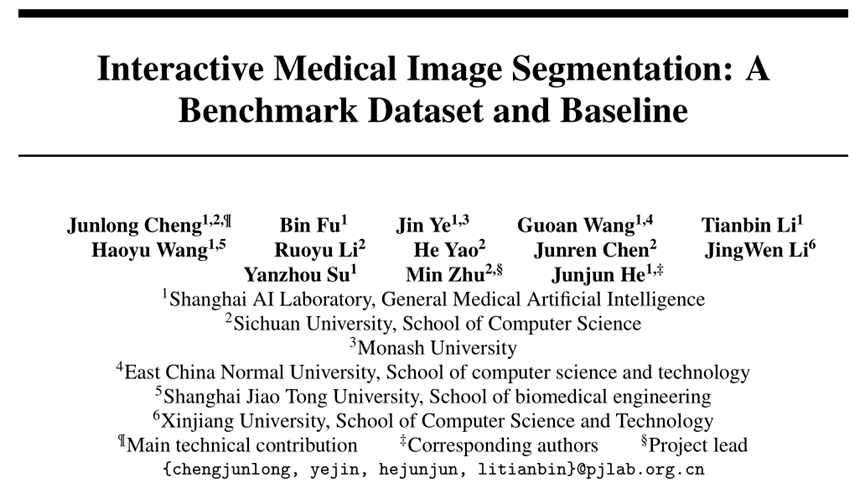

图1. IMed-361M示例图像

为突破交互式医学图像分割技术瓶颈,推动人工智能深度融入医疗实践,上海人工智能实验室 GMAI 团队重磅推出 IMIS-Bench,一个交互式医学图像分割基准框架,涵盖大规模数据集IMed-361M和IMIS基线模型。

前所未有的数据规模与掩码数量

IMed-361M数据集是迄今为止规模最大、标注最密集的交互式医学图像分割数据集。通过整合来自多个医学数据平台的640万张图像和3.61亿个掩码,覆盖14种成像模态几乎所有解剖目标和病灶,该数据集为深度学习模型的训练和评估提供了前所未有的支持。